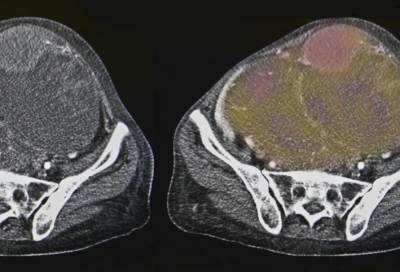

ويقول إن الالتهام الذاتي يعتبر آلية مناعية حيث تلعب دورا حيويا في تدمير الميكروبات التي تصل للخلايا وتحد من السرطانات بتدمير الجزيئات المسرطنة أولا بأول، مما يفتح مستقبلا مجالات البحث عن كيفية تنشيط خاصية الالتهام الذاتي لعلاج السرطانات.

وأكد بدران أن الالتهام الذاتي هو حارس أمن للمناعة يعمل لمدة 24 ساعة، ويحرس الخلايا من الداخل ويقوم بصيانتها دوريا بطرده للجزئيات الضارة التي تدمرها، ويلتهم ما قد يتحور أو يتمرد ليصبح خلايا سرطانية.

ويضيف أنه ثبت حديثا أن الصوم يحمي الخلايا من الفناء المبرمج كما يحميها من التلف مشيرا إلى أن اختلال الالتهام الذاتي يمهد للإصابة بالسرطانات والعدوى المتكررة والشيخوخة المبكرة ونقص المناعة ويزيد من فرص الإصابة بالزهايمر.